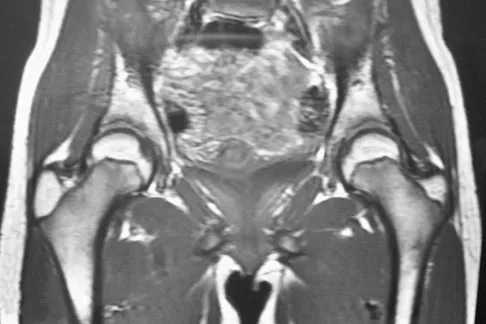

A 15-year-old girl who swims the breaststroke has had hip pain after training excessively for a national level competition. Based on the MRI scans shown in Figures 5a through 5c, what is the most likely diagnosis?

Explanation

The MRI scans reveal open physes but no evidence of a slipped capital femoral epiphysis, labral tear, or acetabular dysplasia. The femoral neck does not show evidence of a fracture. The muscle tear seen on the right side lies near the musculotendinous junction of the external rotators of the hip at the level of the lesser trochanter, representing the obturator externus. This is consistent with the forced motion required for the breaststroke kick. Grote K, Lincoln TL, Gamble JG: Hip adductor injury in competitive swimmers. Am J Sports Med 2004;32:104-108.